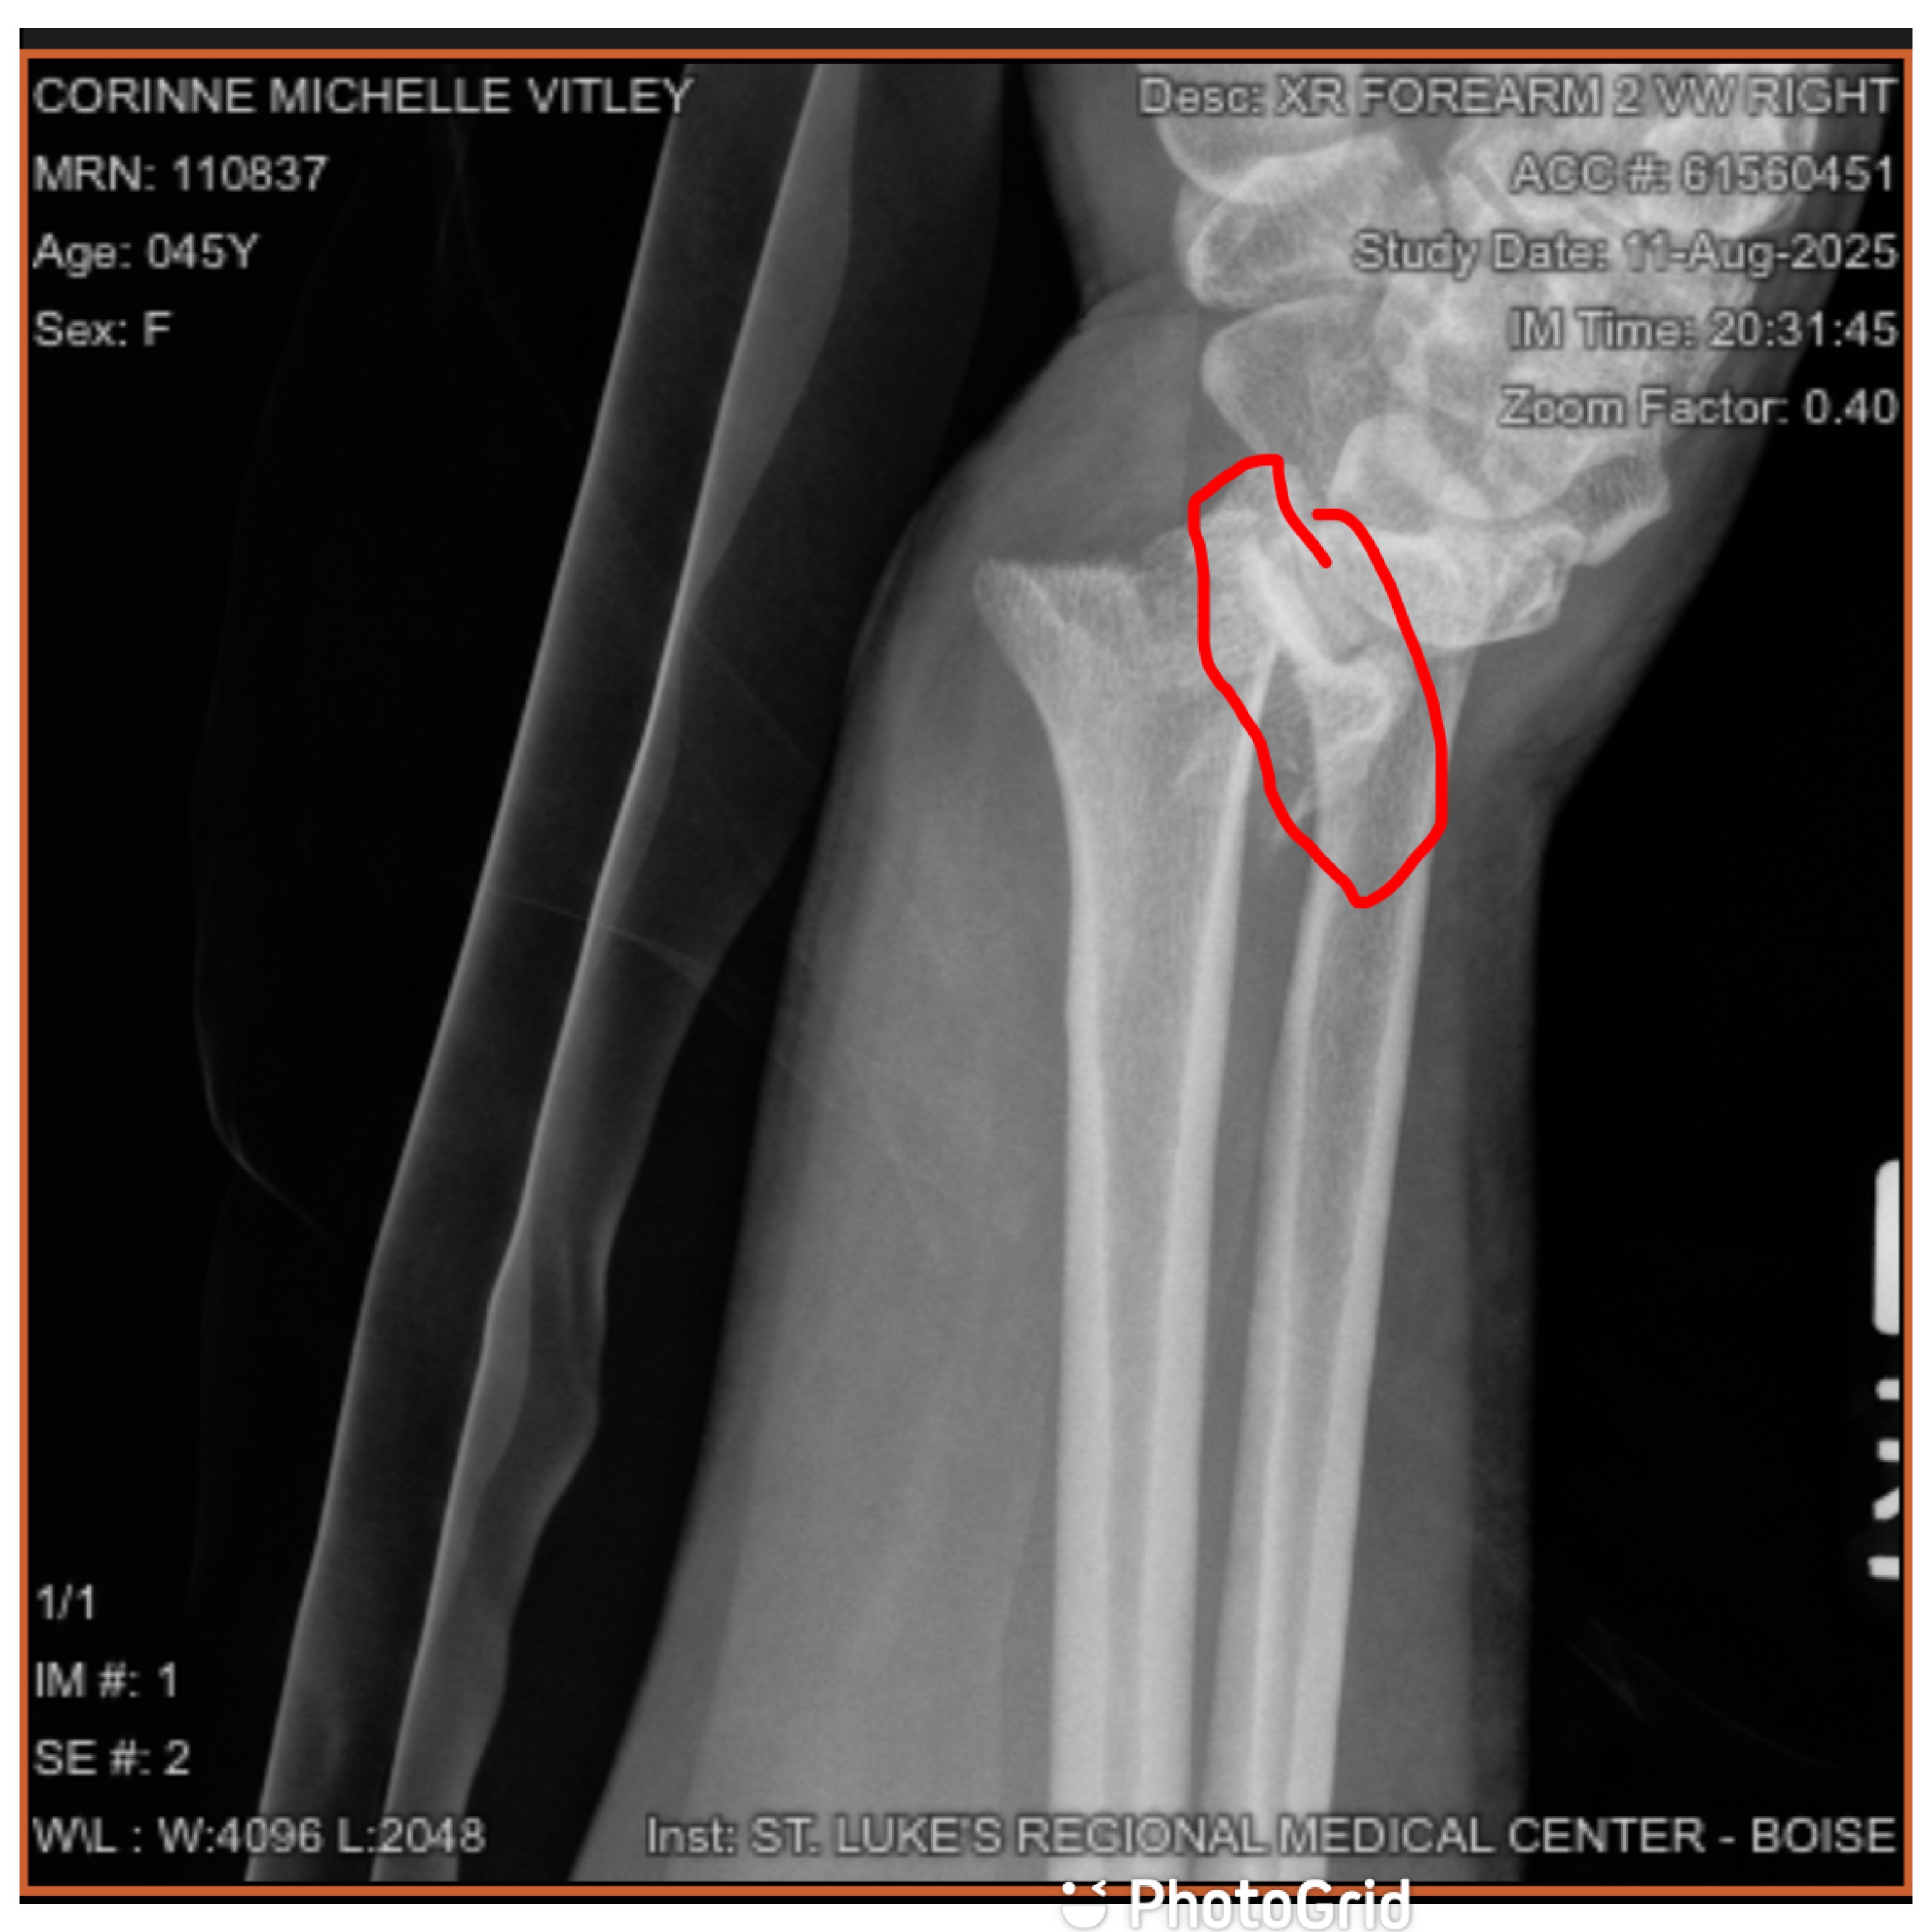

The injury turned out to be far worse than a simple break. On August 22nd, I underwent major surgery. Surgeons had to put my wrist back together with eight pins and two plates, even pinning the head of my radius back on. The recovery has been painful, slow, and overwhelming.